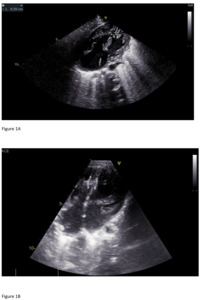

The final echocardiogram showed Pulmonary Artery banding with a max PG of 35 mmHg (mean 17.6 mmHg), small residual flow from the left to right by the ventricular septal defect closure device, and a second apical muscular ventricular septal defect with left-to-right flow with a PG of 24 mmHg, 1+/4+ regurgitation of the left atrioventricular valve with a PG of 75 mmHg, and an intact atrial septum. (Figure 2)